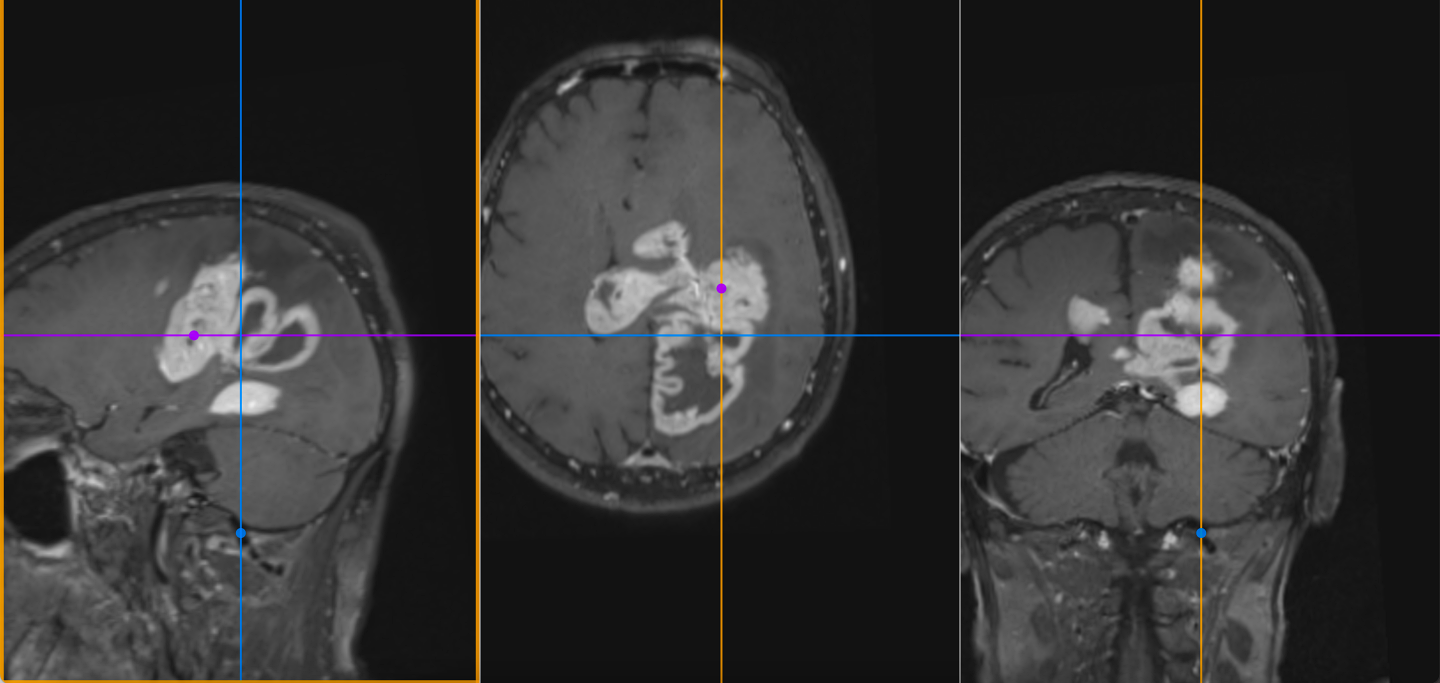

Chirurgia – rol central, dar nu curativ

Chirurgia reprezintă primul pas terapeutic și unul dintre cei mai importanți factori prognostici modificabili.

Conceptul actual este cel de rezecție maximală sigură, care implică:

- îndepărtarea cât mai extinsă a tumorii vizibile

- conservarea funcțiilor neurologice esențiale

Extensia rezecției este direct corelată cu supraviețuirea, însă beneficiul se pierde dacă este însoțit de deficit neurologic semnificativ.

Tehnologiile moderne au crescut semnificativ siguranța:

- fluorescența 5-ALA permite identificarea țesutului tumoral activ

- neuronavigația oferă orientare spațială precisă

- monitorizarea neurofiziologică protejează funcțiile motorii

- chirurgia awake permite cartografierea limbajului și a funcțiilor cognitive

În practică, fiecare intervenție este o negociere fină între radicalitate și funcție.

- Obligatoriu RMN cerebral cu contrast și protocol 3D pentru neuronavigație.

- Mijloace: microscop operator, neuronavigație, monitorizare neurofiziologică intraoperatorie (awake surgery), fluorescență 5-ALA.